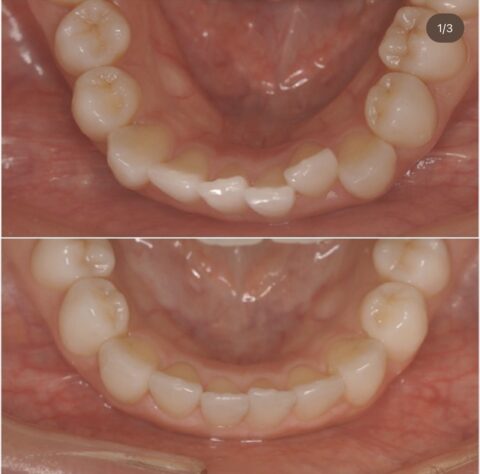

下顎

上顎

上下共に綺麗に並んでいます。

治療終了後に【クリーニング・オフィスホワイトニング】もしたのでとても綺麗な歯並びになりましたね!!